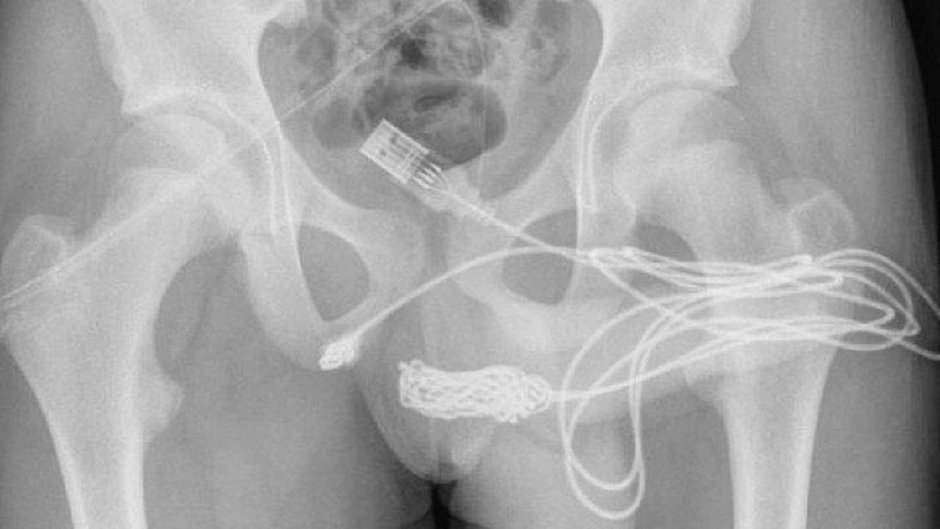

Depois que exame de raio-X revelou o tamanho exato e a posição do cabo, o adolescente foi encaminhado para a sala de cirurgia.

Os cirurgiões cortaram os músculos ao redor do pênis e do escroto e então e removeram cabo.